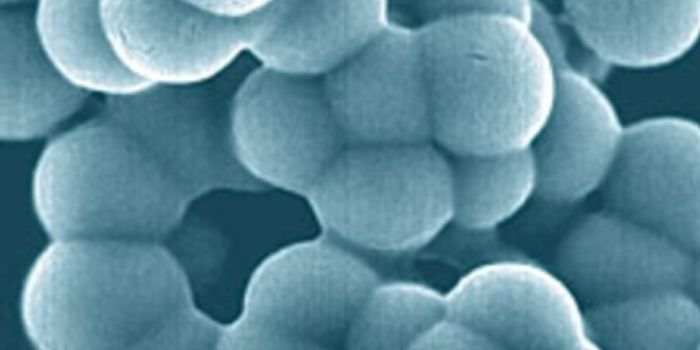

JUN 30, 2016MicrobiologyNanobacteria were proposed to be, as the name suggests, nano-sized bacteria. Researchers tend to agree that cells must b ...